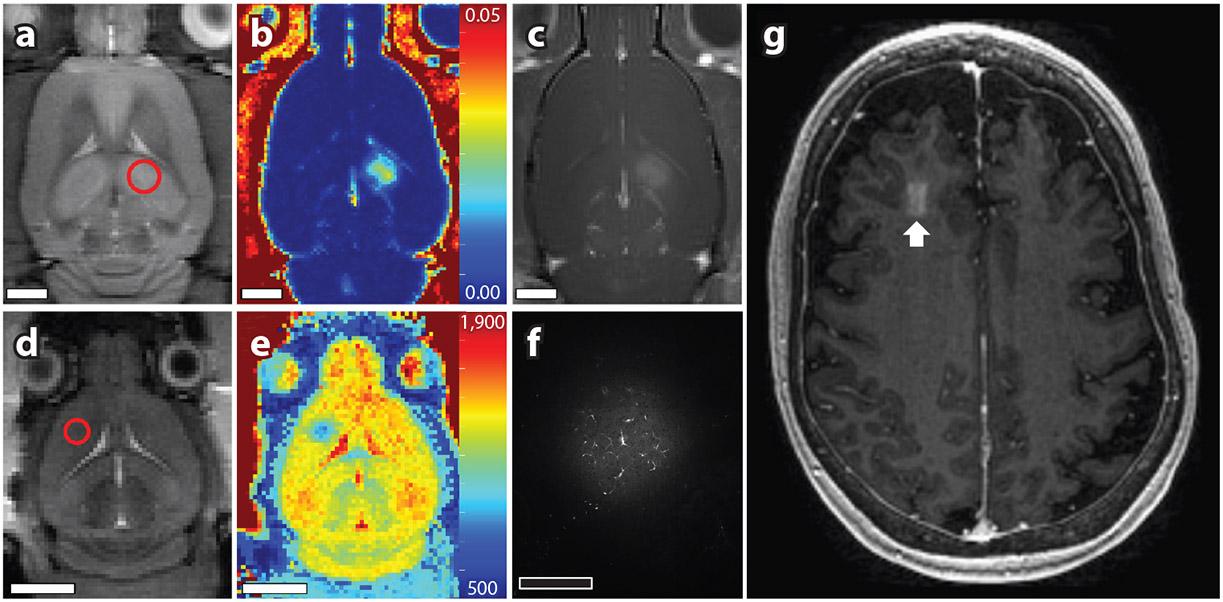

Specialized features of vasculature in the central nervous system greatly limit therapeutic treatment options for many neuropathologies. Focused ultrasound, in combination with circulating microbubbles, can be used to transiently and noninvasively increase cerebrovascular permeability with a high level of spatial precision. For minutes to hours following sonication, drugs can be administered systemically to extravasate in the targeted brain regions and exert a therapeutic effect, after which permeability returns to baseline levels. With the wide range of therapeutic agents that can be delivered using this approach and the growing clinical need, focused ultrasound and microbubble (FUS+MB) exposure in the brain has entered human testing to assess safety. This review outlines the use of FUS+MB-mediated cerebrovascular permeability enhancement as a drug delivery technique, details several technical and biological considerations of this approach, summarizes results from the clinical trials conducted to date, and discusses the future direction of the field.

中枢神经系统血管的特殊结构极大地限制了许多神经病理学的治疗选择。聚焦超声联合循环微泡可用于短暂且非侵入性地增加脑血管通透性,具有很高的空间精度。在超声处理后的几分钟到几个小时内,药物可以全身给药,使药物外渗到目标脑区并发挥治疗作用,之后通透性恢复到基线水平。由于可以使用这种方法递送广泛的治疗剂,并且临床需求不断增长,因此聚焦超声和微泡(FUS+MB)在大脑中的暴露已进入人体测试以评估安全性。本文综述了 FUS+MB 介导的脑血管通透性增强作为一种药物递送技术的应用,详细介绍了该方法的几个技术和生物学方面的考虑因素,总结了迄今为止进行的临床试验结果,并讨论了该领域的未来发展方向。